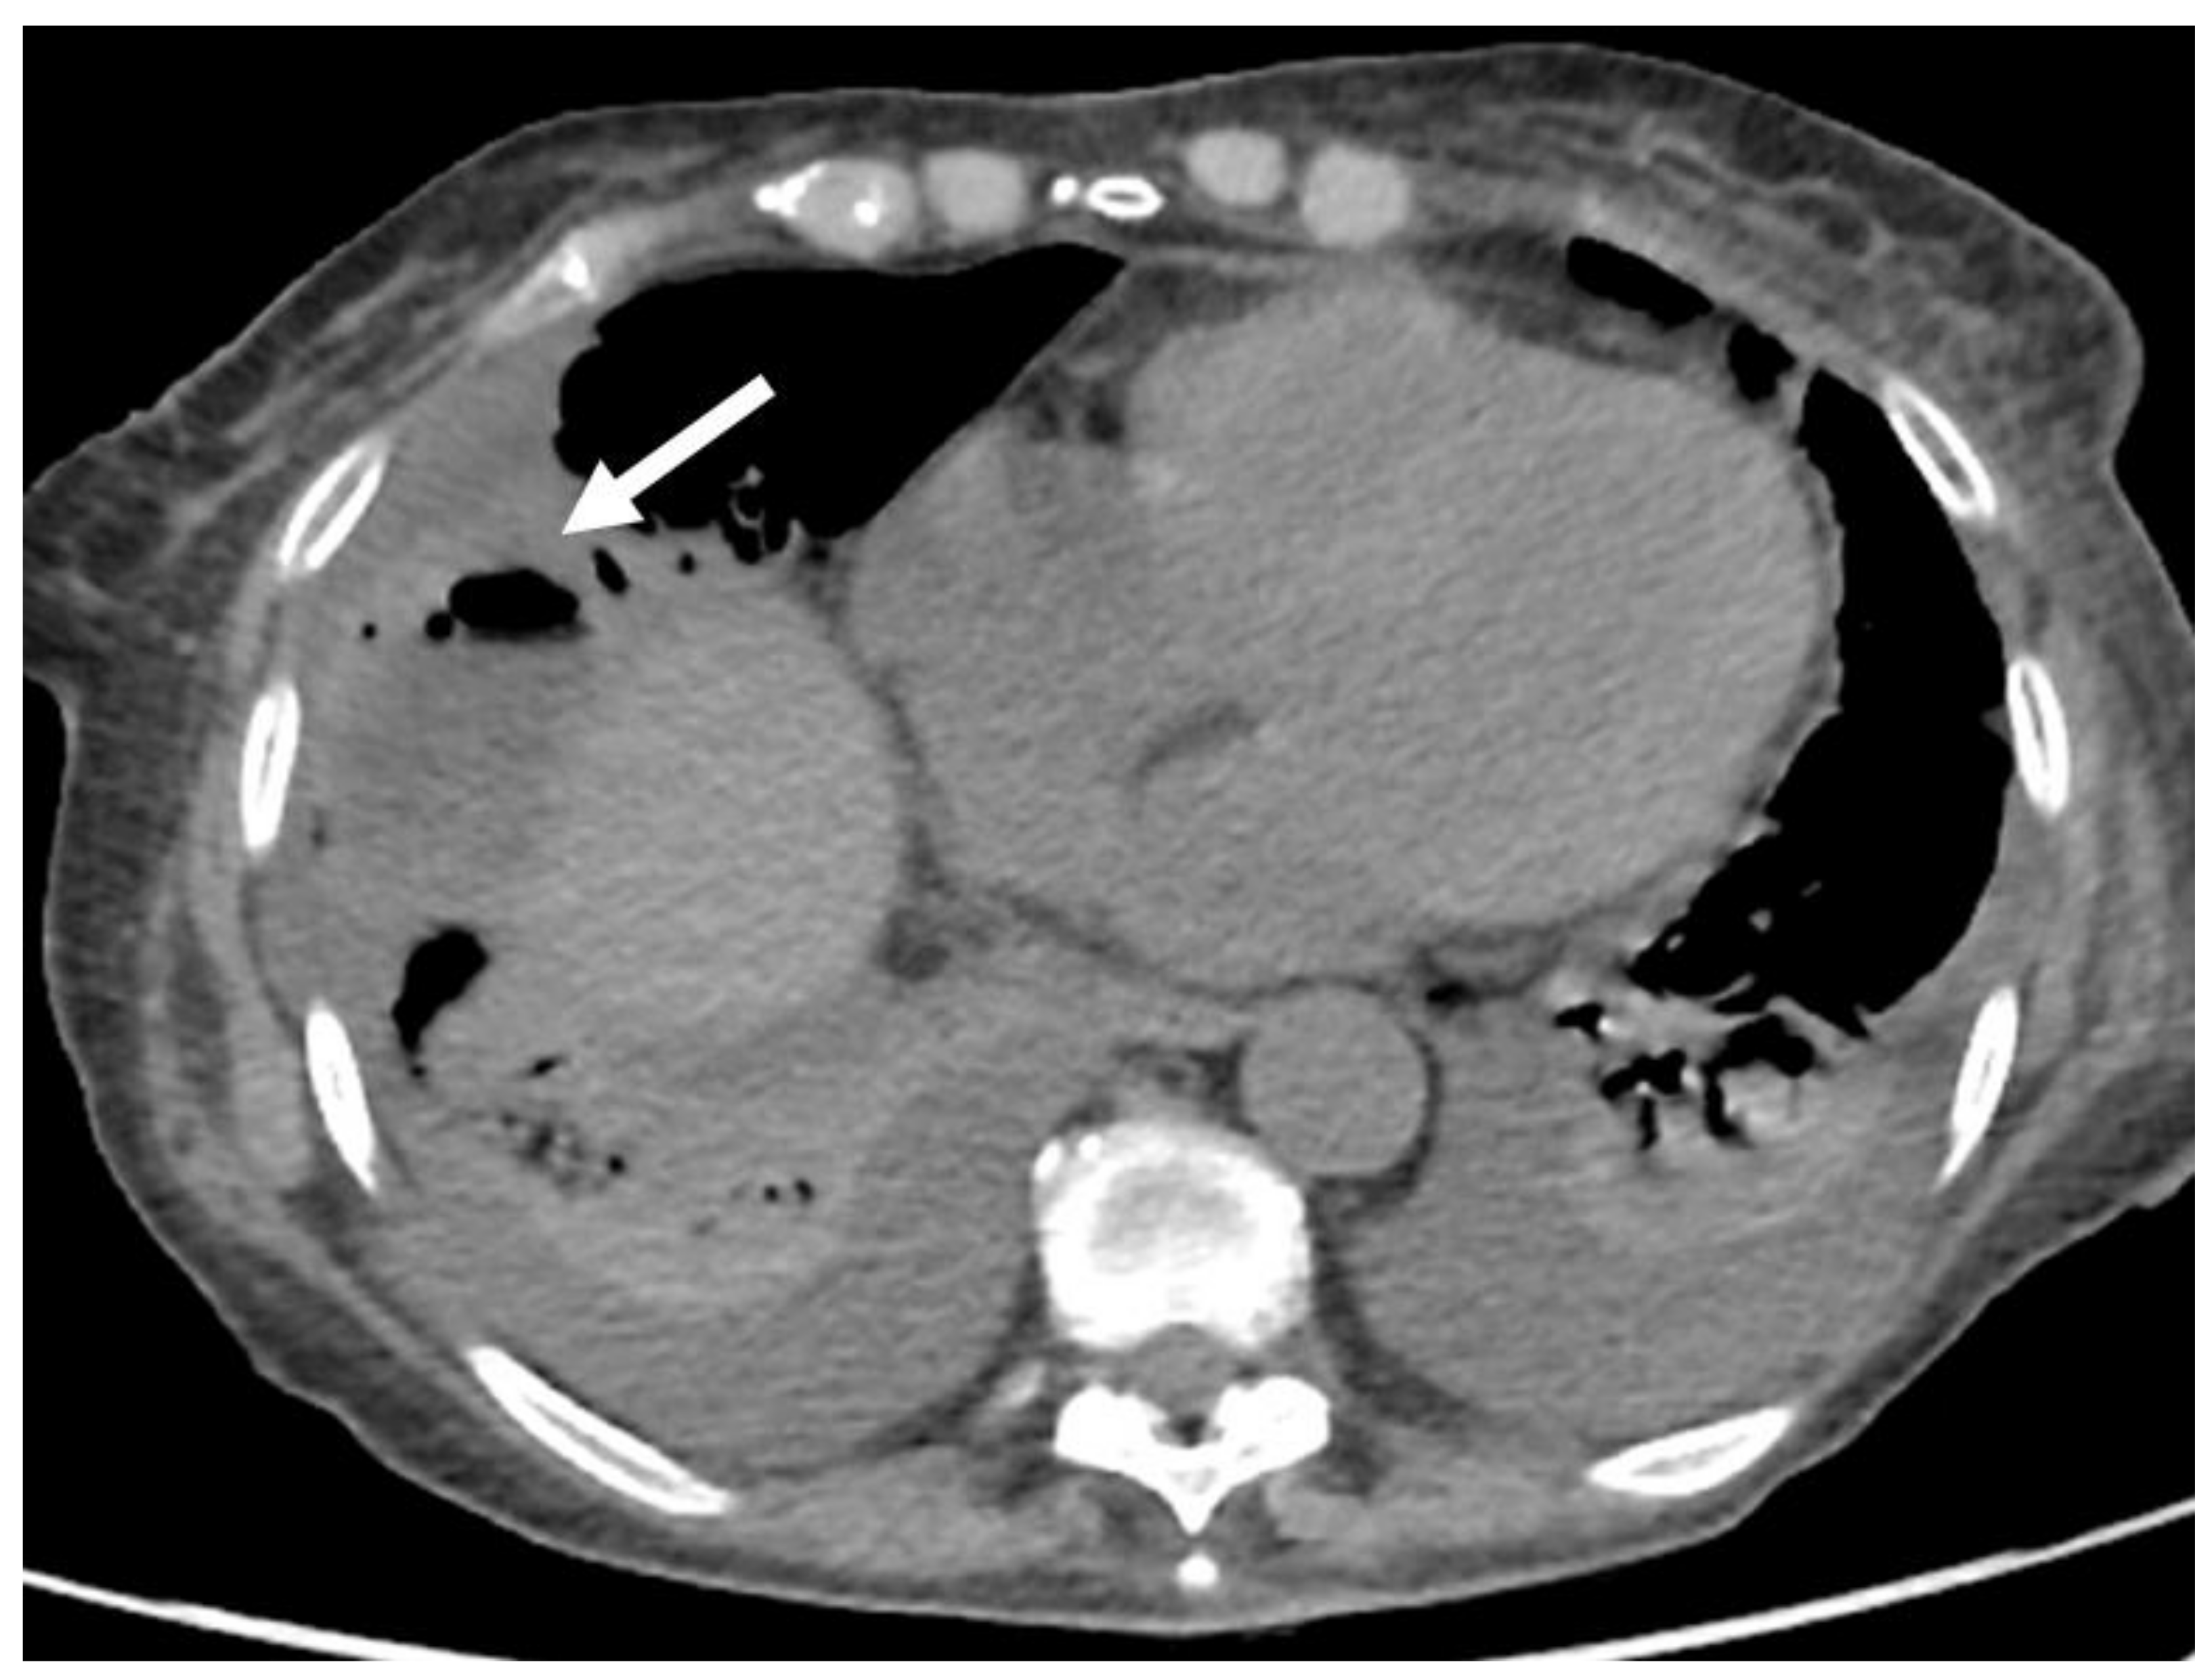

- Granata, V.; Grassi, R.; Fusco, R.; Belli, A.; Cutolo, C.; Pradella, S.; Grazzini, G.; La Porta, M.; Brunese, M.C.; De Muzio, F.; et al. Diagnostic evaluation and ablation treatments assessment in hepatocellular carcinoma. Infect. Agents Cancer 2021, 16, 53. [Google Scholar] [CrossRef] [PubMed]

- Izzo, F.; Granata, V.; Grassi, R.; Fusco, R.; Palaia, R.; Delrio, P.; Carrafiello, G.; Azoulay, D.; Petrillo, A.; Curley, S.A. Radiofrequency Ablation and Microwave Ablation in Liver Tumors: An Update. Oncologist 2019, 24, e990–e1005. [Google Scholar] [CrossRef] [Green Version]